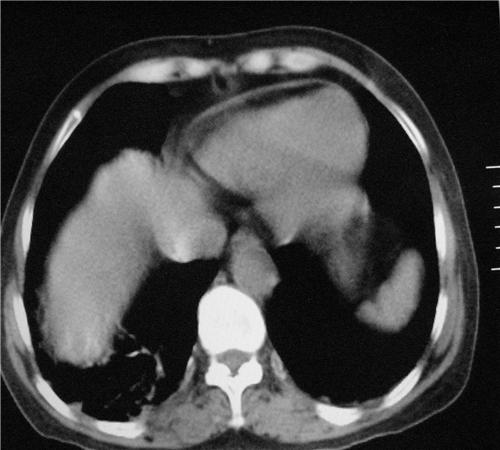

标题: CT26849:女67岁反复胸痛两天余,临床考虑夹层。 [打印本页]

标题: CT26849:女67岁反复胸痛两天余,临床考虑夹层。

双下肺感染,右侧显著。有无夹层,增强扫描后再诊断。

1.考虑双肺感染,右侧为重;2.建议ct增强或mri排除主动脉夹层

双下肺感染,右侧显著。有无夹层,增强扫描后再诊断。食道未见异常。